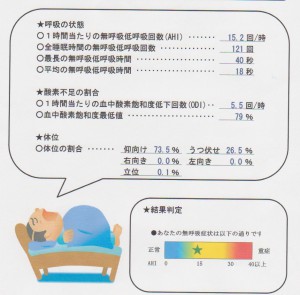

とある大学病院の呼吸器内科から紹介されたKさん。中等度の睡眠時無呼吸との診断であった。睡眠時の1時間当たりの無呼吸低呼吸回数は26回(大学病院での検査値)であった。マウスピースにより当院にある簡易型検査でこの値は1.3回(正常値は5以下)に落ち着いた。Kさんも、周りからいびきを指摘されなくなり、日中の眠気も少なくなったとのことで、喜ばれた。マウスピースは単純な装置だが、患者さんのQOLを向上させるケースは多い。下記の資料を添付して、紹介元の病院に送った。客観的なデータを自院で出せるようになったことは、大きい。術者や患者さんの治療に対するモチベーションが上がる。(長谷川)

患者さんにお渡しする検査結果(左)マウスピース非装着時、(右)装着時